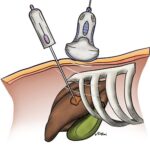

Gan là một trong những tạng lớn nhất trong cơ thể và cũng là tạng thường có bệnh lý nhiều nhất. Bệnh lý gan rất đa dạng và phức tạp. Mặc dù hiện nay các phương pháp chẩn đoán hình ảnh gan – mật đã có nhiều tiến bộ vượt bậc nhưng không phải lúc nào cũng có thể chẩn đoán được bản chất tổn thương của gan và đường mật, khi đó sinh thiết gan là một lựa chọn nhằm tiếp cận với chẩn đoán. Có nhiều kỹ thuật sinh thiết gan trong đó sinh thiết gan dưới hướng dẫn siêu âm là kỹ thuật phổ biến nhất, được áp dụng nhiều nhất…